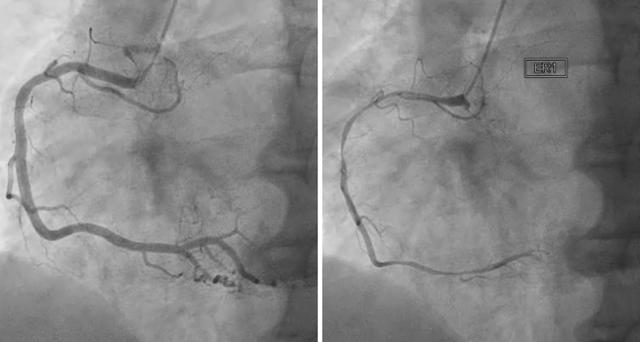

안정 협심증 : 동맥경화로 인해 관상동맥이 만성적으로 협착되어 생기는 경우를 말해요. 동맥경화를 예방하는 것이 좋아요.

불안정 협심증 : 죽상 경화병변이 파열되어 혈전이 생겨서 급작스럽게 협착이 심해져서 생기는 경우를 말해요. 급작스럽게 협착이 심해지므로 예고 없이 증상이 나타날 수 있으며 관상동맥이 좁아져 심장으로 가는 혈류가 급속하게 떨어지므로 가슴 흉통의 증상이 나타날 수 있어요.

이형성 협심증 : 이형성, 변이형 협심증이라고 불리며 죽상 경화병변이 별로 없음에도 혈관의 연축에 의하여 혈류 장애가 발생해서 생기는 경우인데요. 혈관이 수축되어 혈류의 흐름이 원활하게 이루어지지 않아 생기게 되는데 젊은 사람에게도 나타날 수 있고 안정을 취하고 있는 상황에서도 증상이 나타날 수 있어요.